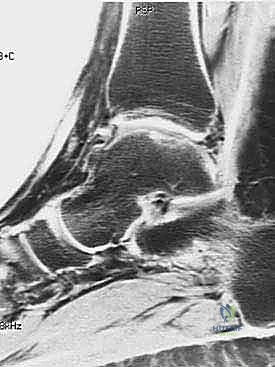

- التصوير بالرنين المغناطيسي (MRI): هو المعيار الذهبي لتشخيص آفات الغضروف العظمي. يتيح الرنين المغناطيسي عالي الدقة للدكتور هطيف رؤية الغضروف بوضوح، تحديد حجم الآفة، عمقها، وموقعها بدقة متناهية، بالإضافة إلى تقييم العظم الكامن تحتها.

- التصوير المقطعي المحوسب (CT Scan): يُطلب أحياناً للحصول على تفاصيل أدق حول البنية العظمية للآفة، خاصة إذا كان هناك تخطيط لترقيع عظمي مصاحب.